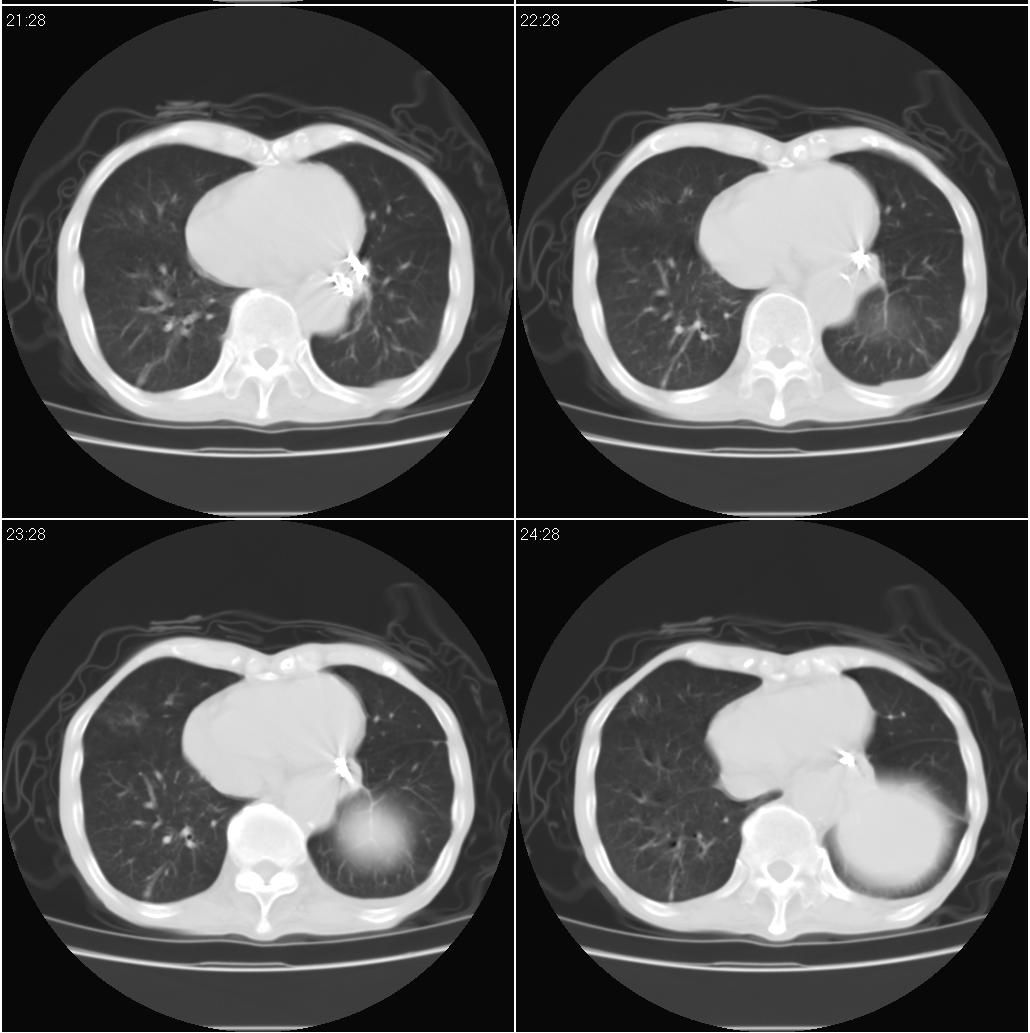

标题: CT15789:男性,72岁。食管癌术后14年。 [打印本页]

痰培养:见葡萄球菌,霉菌少量生长。(此片系外院所作,仅提供了增强后的ct值为100hu,中心的坏死部分无强化,患者现在身体状况欠佳,为恶液质状态)

考虑右肺下叶感染性病变(肺脓肿?);建议抗炎治疗后复查。

符合机遇性感染,真菌可能性大。

该患者通过抗炎治疗明显好转:当时患者消瘦,实是因为患者进食量不多。患者有食道癌,因发生原发肺癌的机率并不高,当时的ct片除了增强感觉有强化外(其实这信息也并不确定,因为是外院ct),其实并没有发现支气管腔改变等直接征象。经过治疗,患者现在一般情况良好。以下是9月22日的复查片,发现病灶吸收明显。纵隔窗就不上传了。